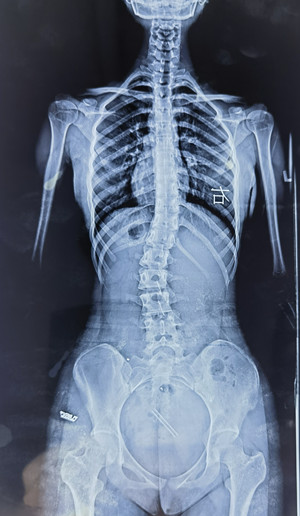

脊柱側(cè)彎拍X片

我的孩子可能脊柱側(cè)彎了,想拍一個(gè) “ 站立式全脊柱正側(cè)位X片 ” 。

您也可以給醫(yī)生看上圖,問下醫(yī)生能不能拍這樣的X片(并不是所有醫(yī)院都有能力拍這樣的X片)。